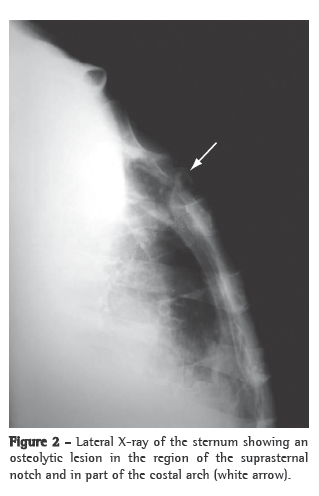

Treatment with ciprofloxacin and clindamycin was initiated. The blood workup revealed normochromic normocytic anemia, the PPD test was positive (induration = 15 mm), HIV testing (ELISA) was negative, and erythrocyte sedimentation rate (ESR) was 48 mm/h. Imaging studies (anterior and lateral chest X-rays) revealed no pleuropulmonary findings suggestive of previous or active TB. A lateral X-ray of the sternum revealed an osteolytic lesion in the region of the suprasternal notch and the first costal arches (Figure 2). A CT scan of the chest revealed an osteolytic lesion in the suprasternal notch, without mediastinal invasion, as well as bilateral transudative pleural effusion related to the clinical profile of pulmonary hypertension and decompensated heart failure (Figure 3). In addition, technetium triphasic scintigraphy showed no increased radiotracer uptake in the lesion. The swab specimen revealed Gram-positive cocci in pairs, and culture was positive for multidrug-resistant Staphylococcus aureus and negative for fungi and mycobacteria after 70 days of incubation. The antibiotic regimen was changed to oxacillin. The result of the histopathological examination of the sternal lesion revealed caseous granuloma. For PCR analysis (Álvaro Laboratory, Cascavel, Brazil), a second sternal biopsy was performed, and the empirical treatment for TB using regimen I (rifampin, isoniazid and pyrazinamide) was initiated. The patient presented a favorable response. The PCR analysis was positive for Mycobacterium tuberculosis, confirming the diagnosis of tuberculous sternal osteomyelitis.

From a radiological standpoint, sternal TB can present the following patterns of bone destruction: osteolytic lesions; periosteal reaction; enhancement patterns; and soft tissue abscess with or without internal calcium formations.(6) These findings, which are not exclusive to sternal TB, can be found in aggressive infections such as actinomycosis.(8)

Although CT does not appear to have any advantage over sternum X-ray in the evaluation of bone involvement, it is significantly superior in the evaluation of perilesional soft tissues, mediastinal involvement and pulmonary involvement.(5-9) Magnetic resonance imaging is a good option for the evaluation of soft tissues and bone lesions, revealing early alterations in the bone marrow, especially at early stages with normal X-ray findings.(4,5,9) Technetium triphasic scintigraphy has high sensitivity and specificity for the diagnosis of osteomyelitis.(2,4) In the case presented here, there was no increased radiotracer uptake in the sternum or photopenia in the osteolytic lesion, nor were there any other findings consistent with osteomyelitis.